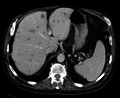

| Axial CT of the abdomen showing multiple liver metastases | |

A liver metastasis is a malignant tumor in the liver that has spread from another organ affected by cancer. The liver is a common site for metastatic disease because of its rich, dual blood supply (the liver receives blood via the hepatic artery and portal vein). Metastatic tumors in the liver are 20 times more common than primary tumors. In 50% of all cases the primary tumor is of the gastrointestinal tract, other common sites include the breast, ovaries, bronchus and kidney.

- Ultrasound scan and CT scan - multiple filling defects.

- CT scan